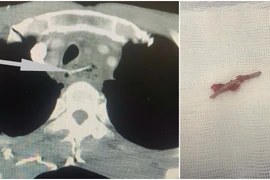

Bệnh viện Nhi Đồng 1, TPHCM vừa tiếp nhận một trường hợp nuốt dị vật đặc biệt nguy hiểm. Bệnh nhi là bé N.P.T., 3 tuổi, nuốt dị vật hình cây thánh giá nằm ở thực quản nguy cơ xuyên vào trung thất đe dọa tính mạng.